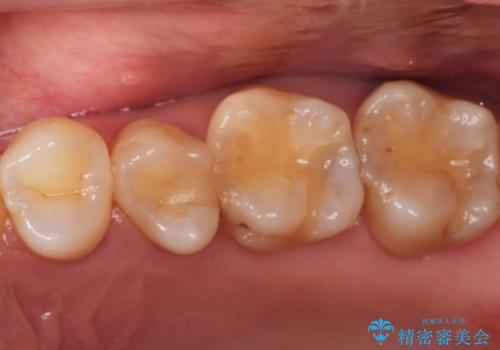

【セラミックインレー】定期検診で見つかった虫歯。

- 歯と歯の間で見つかりづらい虫歯でしたが、顕微鏡で確認し患者様に説明することで理解していただき、セラミックインレーにて修復治療を行いました。

以前にプラスチックの材料で修復した箇所が虫歯として見つかることはよくあります。